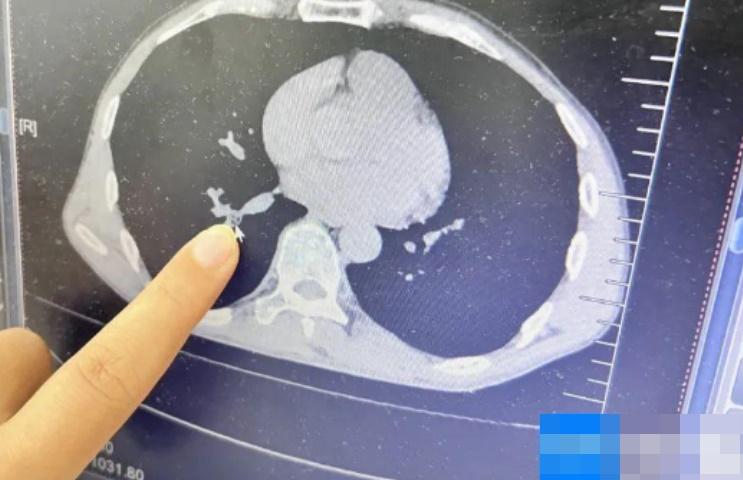

綜合《紅星新聞》等內地媒體報道,海口一名58歲男子於8月就診前3天的一個晚上,睡夢中的他,感覺有蟲子爬進了鼻孔,受刺激後出現嗆咳,但不是特別劇烈,他當時沒在意,隨後反覆出現咳嗽、咳黃痰,口腔裡有一種曱甴的異味和臭味,還很明顯,決定到醫院求醫。海南醫院呼吸與危重症醫生林玲表示,當時為病人做胸部CT檢查,發現患者右下葉外後基底段有一塊陰影,結合病史,考慮是有異物。